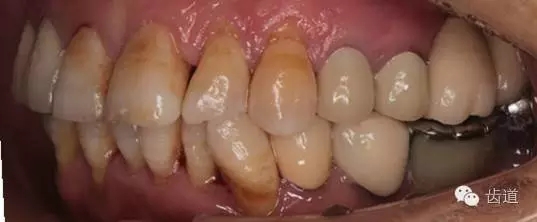

1、全口正面觀

1、治療前

2、治療后